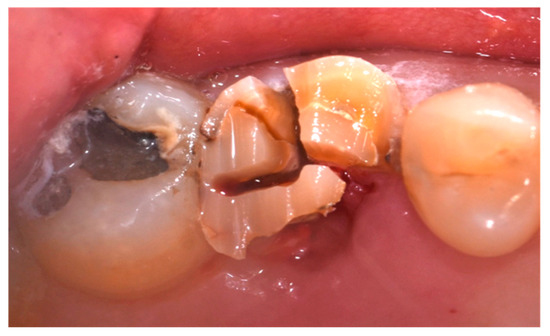

- Cause of extraction: caries, orthodontic reasons, or trauma;

- Presence of at least one severely compromised dental element to be extracted;